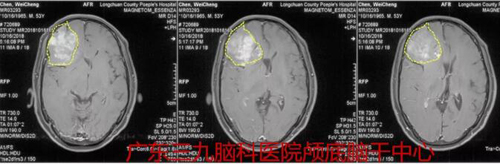

陈某,男,49岁,因“间断头晕伴呕吐1天”于2018年10月17日入院。外院影像结果示:右侧额叶胶质母细胞瘤伴出血。

入院后完善相关检查,于2018年10月18日行“右侧额叶肿瘤并卒中切除术”,术程顺利,病理报告示:(右侧额叶)IDH突变型低级别胶质瘤 WHOⅡ级。

图1:术前CT结示右侧额部团块状的占位,伴有卒中

图2:术前MR示右侧额叶占位性病变,强化不明显,混杂信号,大小约5cm*6cm,考虑肿瘤卒中可能。